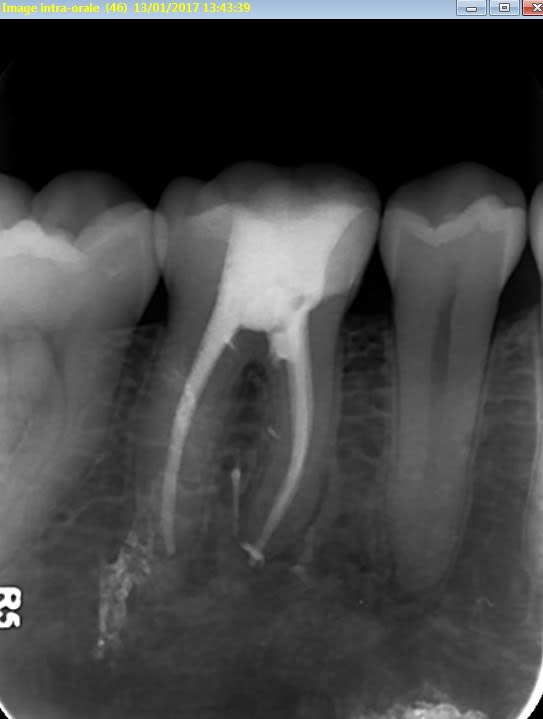

junior® écrivait:

-----------------

> Tiens celle ci c'est pour le plaisir d'offrir et c'est pour Vulpi qui avait

> l'air de se moquer de moi hier😊:

> -> cas d'aujourd'hui

> - dent calcifiée comme jamais

> - je réussis à retrouvé le canal au niveau des 3/4 de la dent avec un insert

> endo fin (radio avec insert ci joint)

> - obturation quasi à l'apex

> - réalisé avec un capodent et non une digue😊😊😊

>

Tu as vu, la 6, en distal la CR ne va pas à la limite, et là, coup de bol c'est un amalgame, parce-qu'avec un SC33 compo...reprise de carie quasi certaine. Je ne suis pas pour ce genre de reconstitution (amg) mais là c'était judicieux, moins délabrant qu'un IC, démontable, et permettant de gérer la partie sous-gingivale.